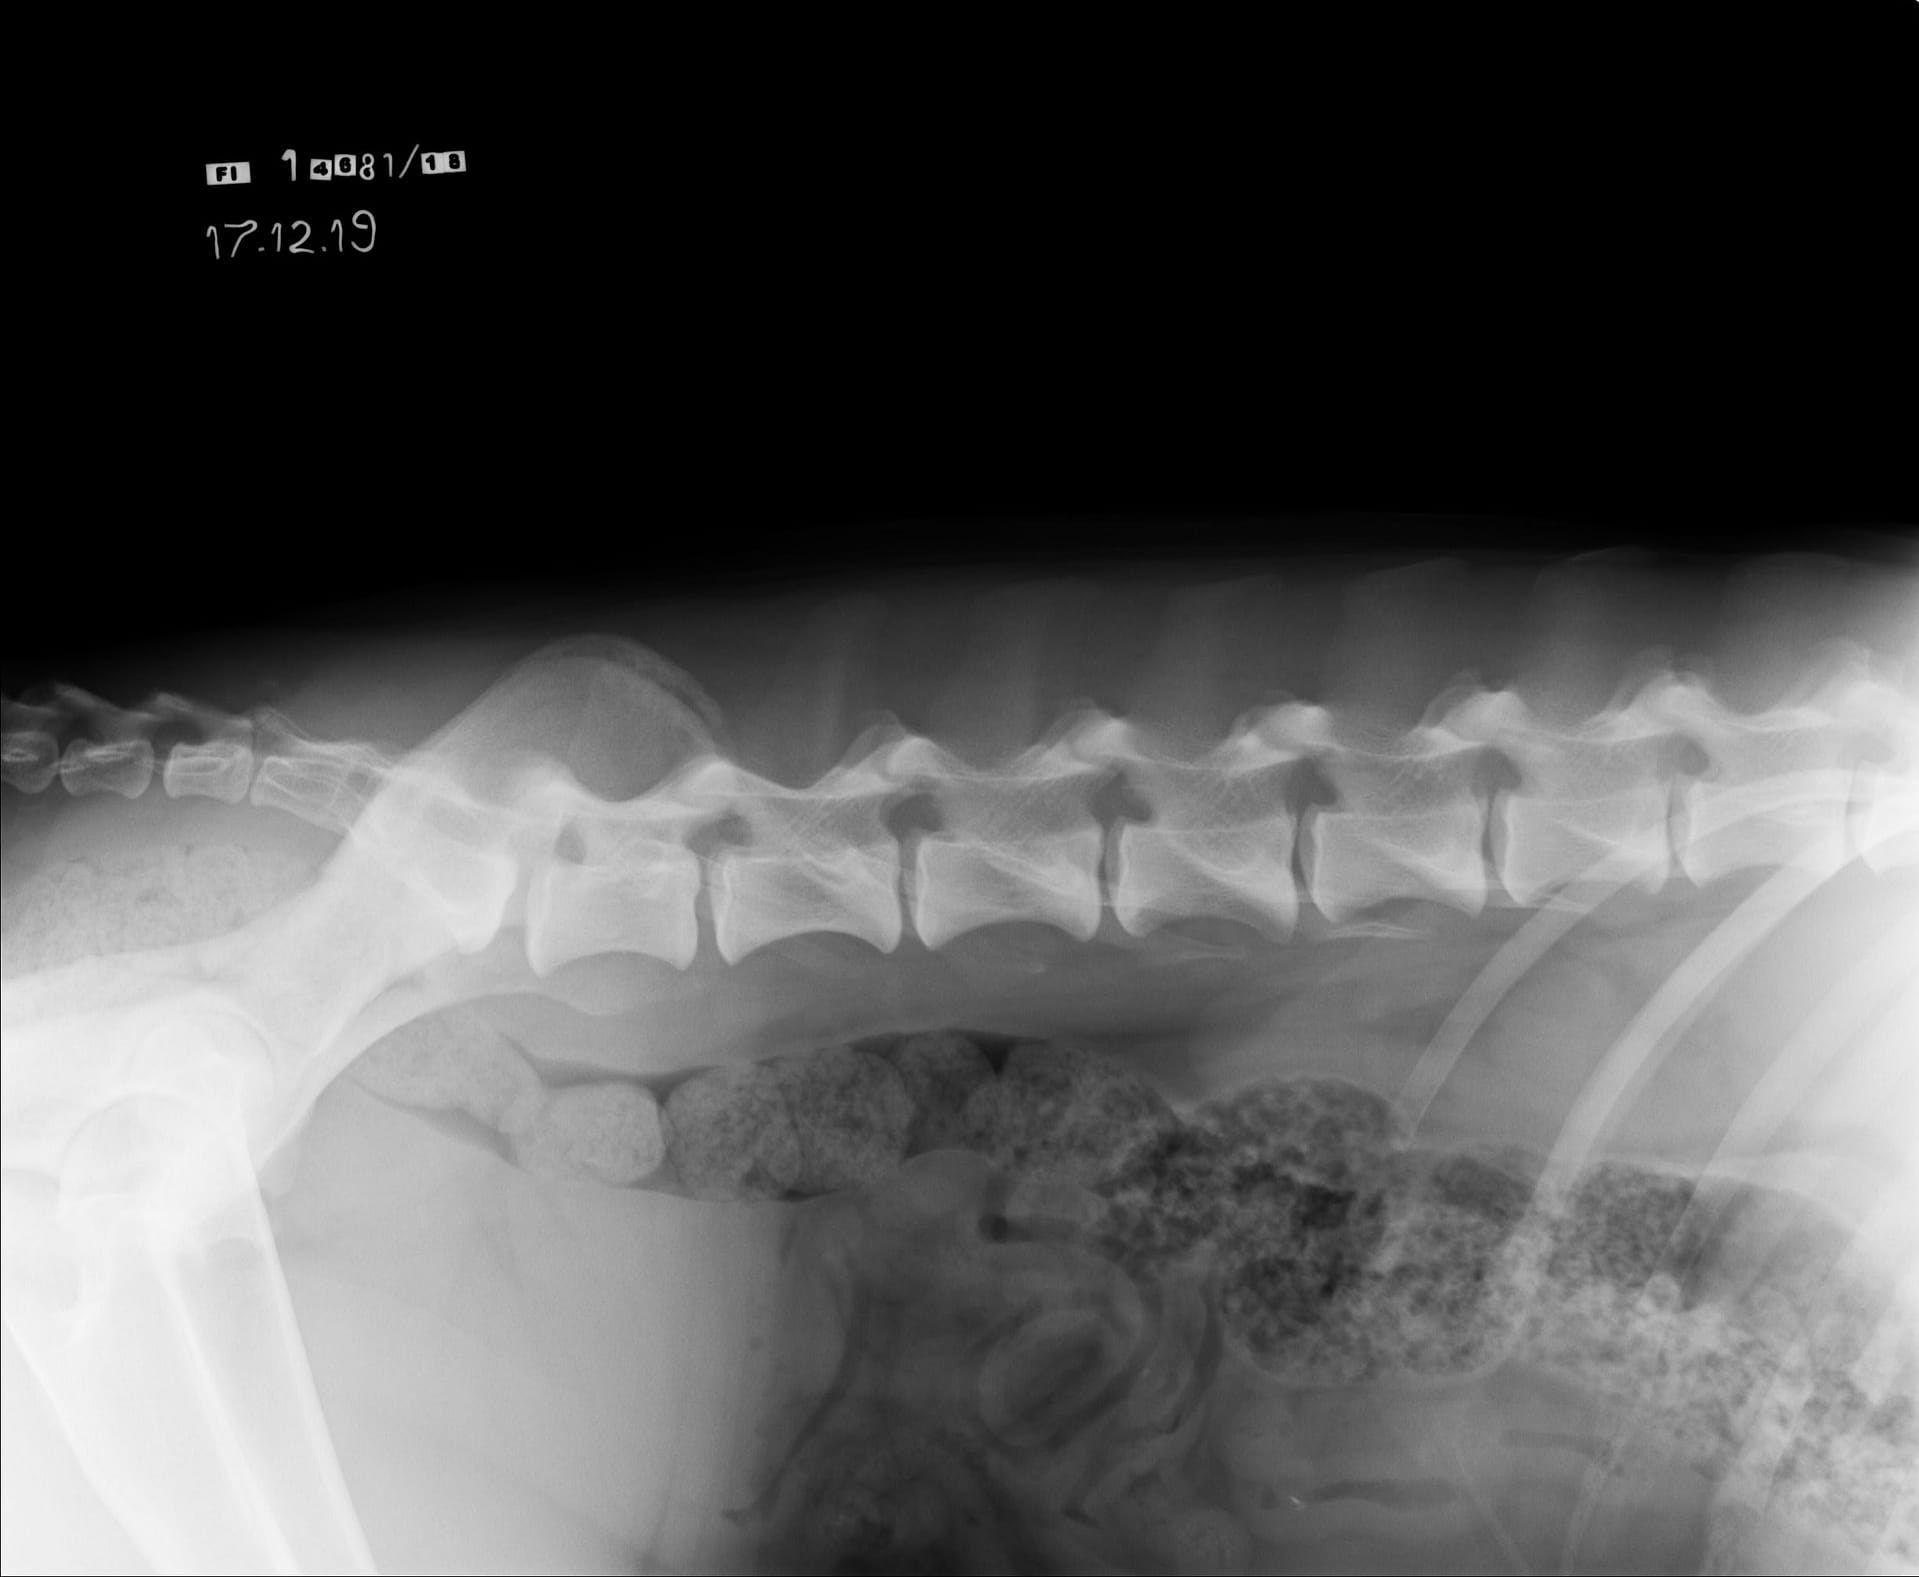

Tähän mennessä Iivo on ollut täysin terve ja Iivo tutkittiin luustoltaan terveeksi joulukuussa 2019. Luonnekuvaukseen (MH, laukausvarma) Iivo osallistui elokuussa 2020.

| Selkä: | LTV0, SP0, VA0 |